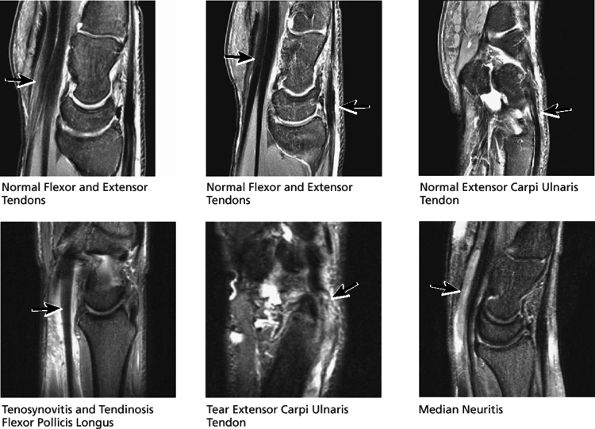

The extensor tendons, including the extensor carpi ulnaris tendon on the ulnar aspect of the wrist, and the extensor pollicis brevis and abductor pollicis longus tendon on the radial aspect of the wrist, for tendinosis, tears, or tenosynovitis

radial aspect of the distal forearm (proximal to the wrist), where the first compartment muscles cross over the second extensor compartment tendons. Tendinosis and tearing of the extensor carpi ulnaris (in compartment 6) is also common and presents as dorsal ulnar-sided pain. The extensor pollicis longus (in compartment 3) can also occasionally tear. The distally retracted, thickened, and frayed end of the torn extensor pollicis longus is often visualized at the level of the proximal carpal row, where the extensor pollicis longus tendon crosses dorsal to the extensor carpi radialis brevis and longus tendons.